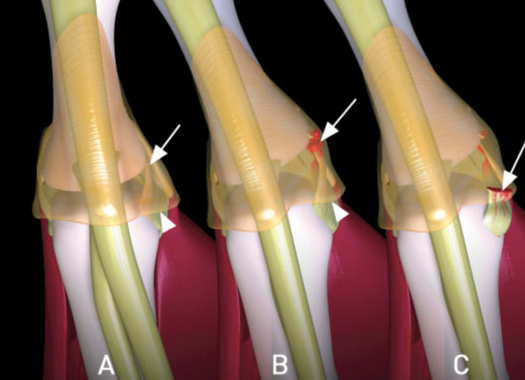

- Steiner Lesion= avulsed ligament w/wout bony attachment is displaced ABOVE ADDUCTOR APONEUROSIS

- won’t heal without surgical repair

What is a stener lesion?

- Displacement of the distal end of the completely ruptured UCL such that it comes to lie SUPERFICIAL and PROXIMAL to ADDUCTOR APONEUROSIS

- Must be operated on!!

- Stener lesion